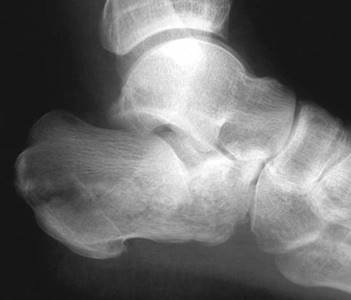

What do you see in this picture and what causes this type of injury?

This is a lateral radiograph showing a displaced talar neck fracture. The subtalar joint appears to be incongruent. I would classify this with the Hawkinโs system as a type II fracture.

T his injury is caused by the application of an axial load to the plantar aspect of the foot. This is a high-energy injury often associated with RTAs.